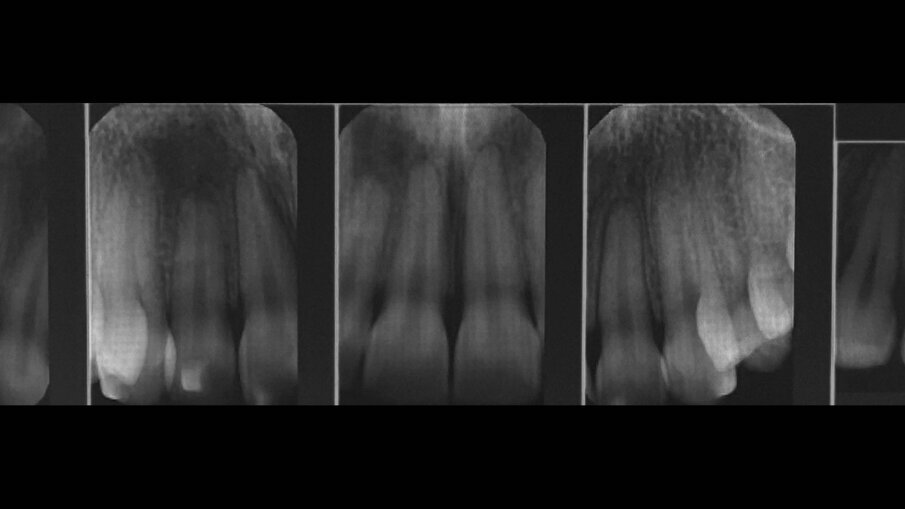

Una paziente di 25 anni si è presentata alla nostra attenzione per risolvere e migliorare il suo sorriso “gengivale”(Fig. 1). In prima visita lo status di rx endorali eseguite con il centratore di Rinn e la tecnica parallela confermavano la diagnosi di eruzione passiva alterata, la mancanza di “luce” negli spazi inter-prossimali e la posizione dei picchi ossei interprossimali rappresentano i segni caratteristici di questa problematica (Fig. 2). Lo studio del caso veniva completato eseguendo le fotografie, intra ed extra orali, la scannerizzazione delle arcate con uno scanner intra-orale e l’esecuzione della CBCT dell’arcata superiore (Fig. 3).

Fig. 2_Status di rx endorali.